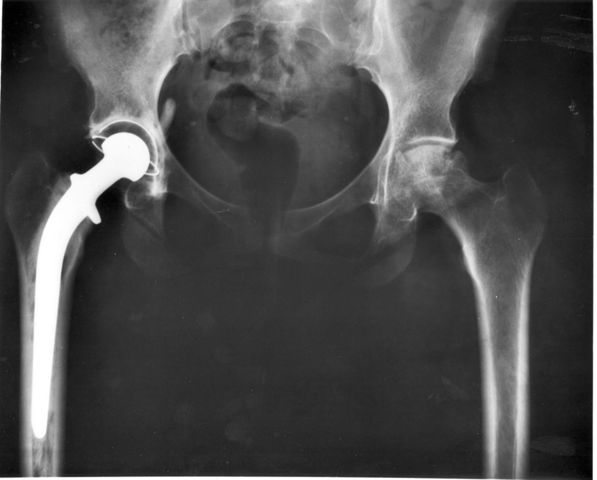

• Metal hip replacement

Metal hip replacement

In 1940 the first metal hip replacement surgery was performed